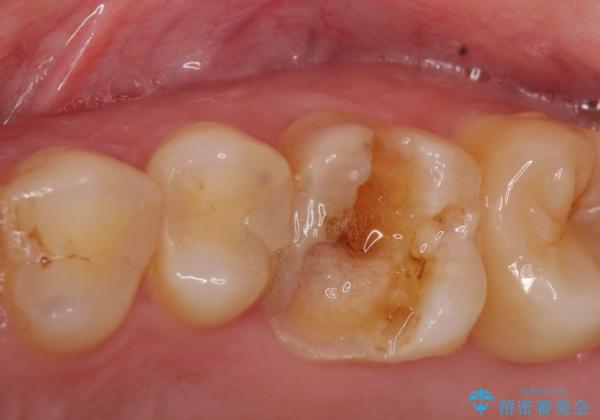

- 左上の奥歯が痛んでものを食べられないといらっしゃった方の症例です。

左上6は虫歯を除去後、神経症状がないことを確認し、オールセラミッククラウンによる補綴を行いました。

左上5は古い樹脂と虫歯を除去後、セラミックインレーによる修復を行いました。